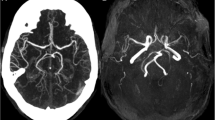

Neuroimaging of patient 2 (adult-onset MELAS). Brain MRIs (a, b) and 123I-IMP SPECT (c) obtained on day 2 of the 2nd SLE show slightly increased DWI/FLAIR signals in the left occipito-temporal cortex and marked hyperperfusion. The MRI/MRA (d–f) obtained on day 6 show increased DWI/FLAIR signals along the cerebral cortex with associated edema and vasodilatation of the left posterior cerebral artery branches. Brain MRIs (g–l) obtained during the active stage of the 3rd SLE show disseminated increased DWI/FLAIR signals confined to the cerebral cortexes. a, d, g–i DWIs, b, e, j–l FLAIR images, c123I-IMP-SPECT, and f MRA

Paroxysmal discharges and focal hyperperfusion were seen in 20 of 24 SLEs (83.3%), and 25 of 26 SLEs (96.2%), respectively. Initial brain lesion spread to adjacent cortex over a few weeks in at least 14 of 44 SLEs (31.8%). Such a progressive spread was more frequently seen in SLEs with delayed-onset seizure than in those without (8/12 vs. 6/32, p = 0.0043) and exclusively in C-SLEs but not in non-classic SLEs (14/29 vs. 0/15, p = 0.0013). Progressive spread was often accompanied by focal hyperperfusion (14/14, 100%) and seizure activity (10/13, 76.9%). A MRA did not show vasospasm but rather vasodilatation of the branches of middle cerebral artery or posterior cerebral artery ipsilateral to acute SLLs in nine SLEs (Fig. 1f). Accordingly, C-SLEs were mainly attributed to single continuous lobular lesions incongruent to vascular territory, extending along the cerebral cortex, and occasionally accompanied by a gradual spread of SLL associated with hyperperfusion and persistent seizure activity, while non-classic SLEs were mainly attributed to multiple sparsely distributed or disseminated small cortical lesions (Figs. 1, 2, 3, 4).

SLEs began with acute onset of symptoms in 42 of 44 SLEs (95.5%), but D-SLEs of 2 adult-onset patients began with ill-defined subacute-onset fluctuating encephalopathy. D-SLEs developed in two adult-onset and two pediatric-onset patients. D-SLEs of the adult-onset patients were characterized by non-specific psychosomatic symptoms such as fatigue, dizziness, headache, decreased concentration, speech alteration, tremor, and disinhibited behaviours. These symptoms were initially thought to be psychogenic or residual non-specific symptoms, resulting in a marked delay of the initiation of therapy; no treatment was initiated until a hospitalization 5 months after the symptoms onset in patient 2. In patient 11, it took 3 months to be recognized as a recurrence of SLEs (Online Resource 1). In patient 11, brain MRIs obtained 16 months after the symptoms onset showed extensive gadolinium enhancement along the gyri of the affected cortexes, indicating not only focal disruption of the BBB, but also same subacute stage of all disseminated lesions (Fig. 2g–i). An EEG also showed periodic synchronous discharges (PSDs) when the patient was being confused (Online Resource 4). While D-SLEs in two pediatric patients began with acute onset of headache and vomiting, both patients were immediately transferred to a hospital and treated with intravenous l-arginine and edaravone on the day of the symptom onset. The clinical pictures of D-SLEs were different between adult-onset and pediatric-onset patients. On brain MRIs, disseminated adjacent small lesions joined with each other causing FLAIR hyperintensity along the cerebral cortex similar to classic SLLs (Fig. 3a–c). A cluster of disseminated spotty DWI hyperintensities was also shown as continuous FLAIR hyperintensities resembling classic SLL (Fig. 4g–l). However, imaging pattern was different between classic SLL and a cluster of adjoining lesions.

It remains controversial whether SLEs are caused by ischemia or not, but endothelial dysfunction is currently considered to play an important role [2, 11,12,13,14,15]. Persistent seizure activity is also implicated in the pathophysiology of slowly progressive spread, by increasing an energy demand under a genetically determined oxidative phosphorylation defect, which causes an imbalance between energy demand and supply, resulting in cortical laminar necrosis in the most vulnerable layer of the cortex [2, 8,9,10]. Extensive oxygen extraction fraction (OEF) reduction in SLLs, as well as in the normal-appearing brain regions have been demonstrated using MR OEF imaging, and more severe dysfunction of the mitochondria is implied at the onset of SLEs [16]. The association between slowly progressive spread and delayed-onset seizure supports hyperexcitability hypothesis. Migraine-like headache at onset could be explained by activation of the trigeminovascular system [17]. Elevated CSF levels of calcitonin gene-related peptide (CGRP), which is a potent vasodilator released from activated perivascular trigeminal nerve endings and implicated in migraine pathophysiology [18], are demonstrated at the early stage of SLEs with prominent vasodilatation of the ipsilateral intracranial arteries (at the 1st SLE of patient 7) [2]. Thus, vasodilatation of intracranial arteries associated with acute SLLs may be explained in part by activation of the trigeminovascular system.